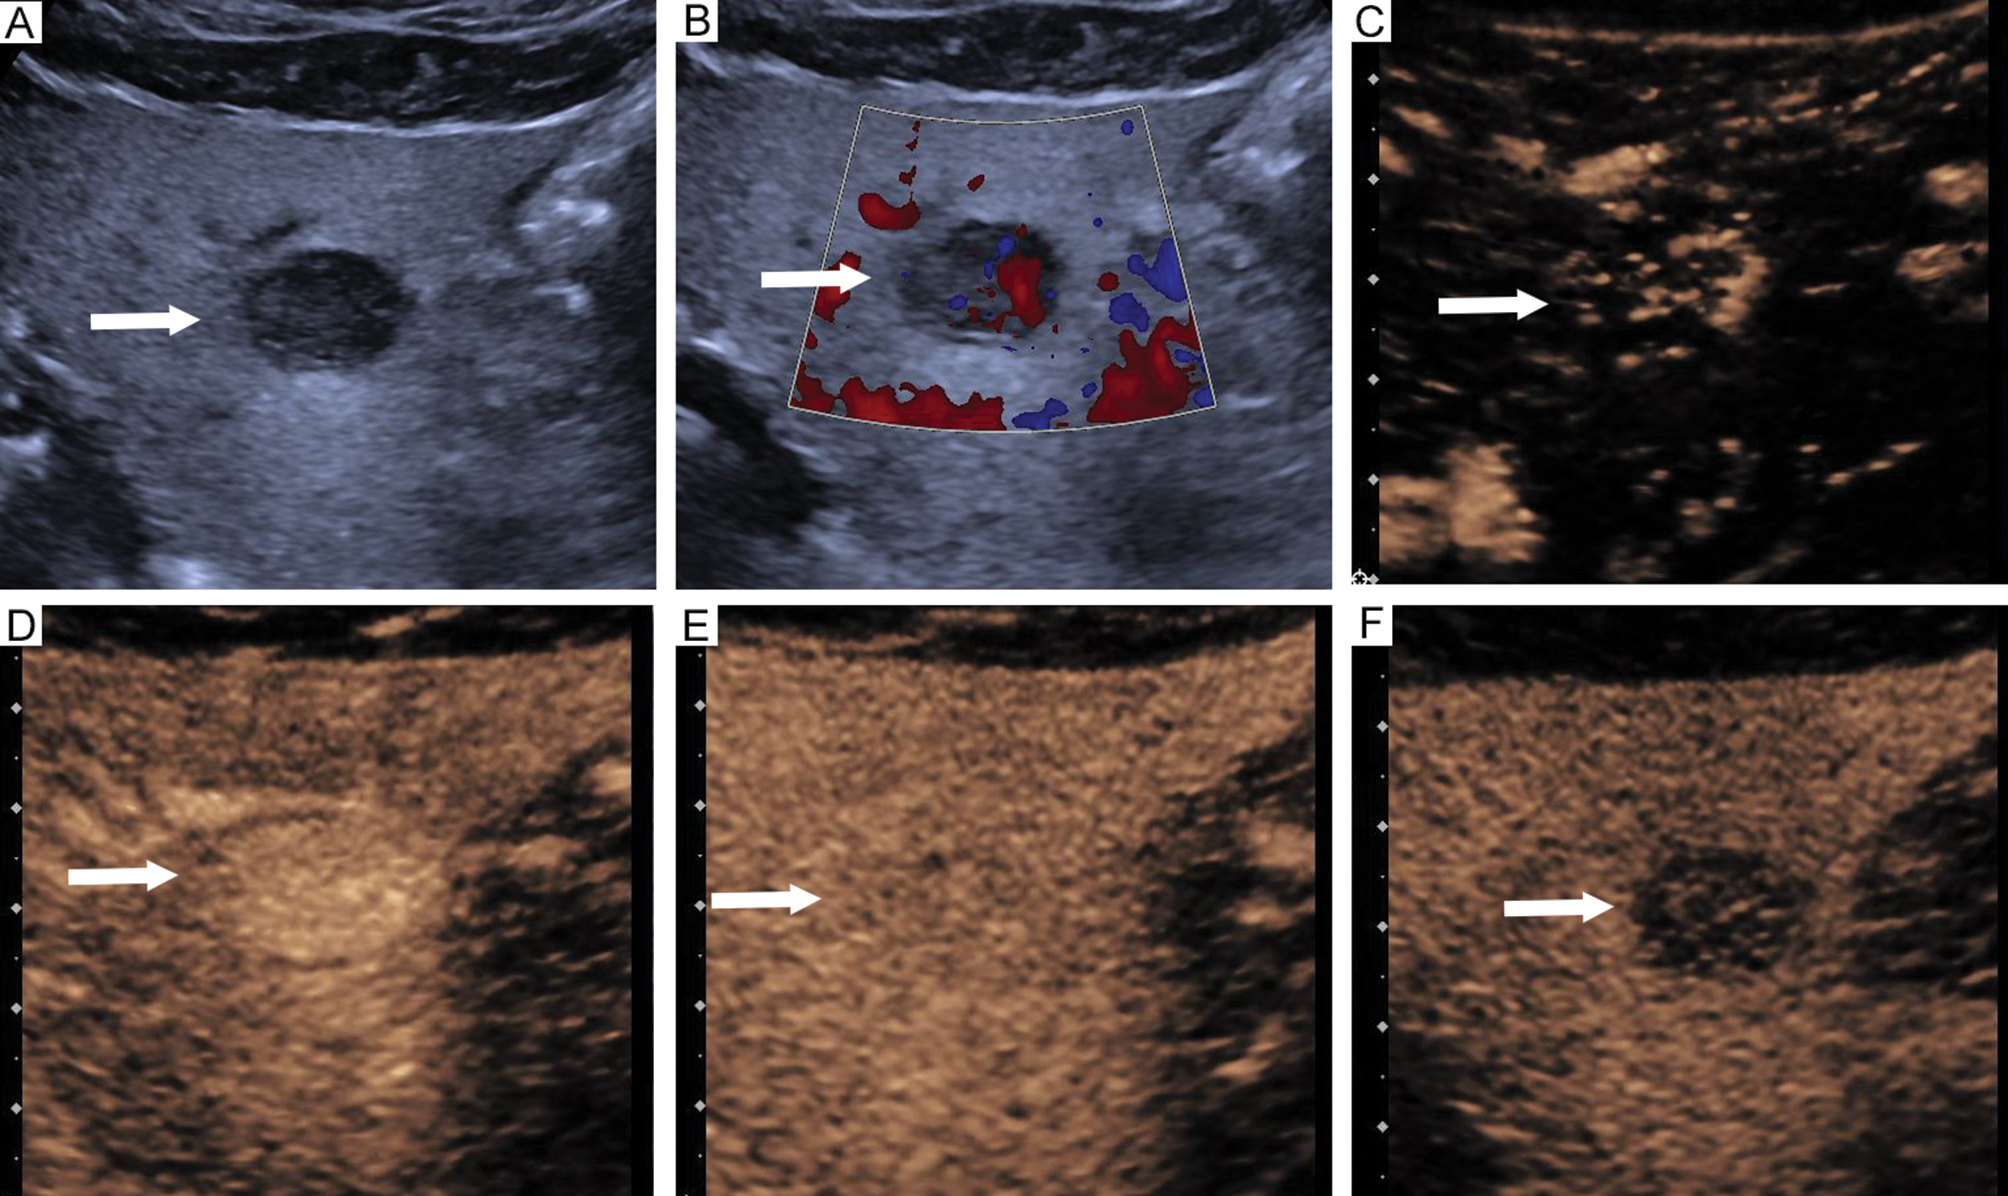

Figure 2 Imaging features of perivascular epithelioid cell tumor in a 69-year-old female. (A) Hyperechoic lesion located in segment 3 (arrow). (B) Presence of larger blood vessels around lesions (arrow). Contrast-enhanced ultrasound revealed (C) Rapid centripetal enhancement at 13 s (arrow), (D) Hyperenhancement in the arterial phase without necrosis at 20 s (arrow), (E) Hyperenhancement in the portal phase at 59 s (arrow), (F) Isoenhancement in the delayed phase at 183 s (arrow).

Figure 3 Imaging features of hepatocellular carcinoma in a 75-year-old male. (A) Hyperechoic lesion located in segment 3 (arrow). (B) Absence of larger blood vessels around lesions (arrow). Contrast-enhanced ultrasound revealed (C) Rapid centripetal enhancement at 15 s (arrow), (D) Hyperenhancement in the arterial phase with necrosis at 24 s (arrow), (E) Hypoenhancement in the portal phase at 67 s (arrow), (F) Hypoenhancement in the delayed phase at 171 s (arrow).

The CUS imaging features of both groups are summarized in Table 2. Significant differences were detected in echogenicity, margins, and the presence of larger blood vessels around lesions between the PEComa and HCC groups (P < 0.05). PEComa lesions were more likely to have a hyperechoic appearance with clear margins and larger blood vessels around lesions compared to HCC lesions (Figures 2 and 3). No significant differences were detected between the two groups with respect to tumor number, location, maximum diameter, morphology, hyperechoic ring, or blood flow on color Doppler imaging (P > 0.05).

Comparisons of CEUS features between the PEComa and HCC groups are provided in Table 3. Necrosis, portal phase enhancement intensity, delayed phase enhancement intensity, and washout time were significantly different between the PEComa and HCC groups (P < 0.05). PEComa lesions were characterized by the absence of necrosis, hyper- or iso-enhancement in the portal phase, isoenhancement in the delayed phase, and a washout time > 180 s compared to HCC (Figures 2 and 3). No significant differences were detected in initial enhancement time, arterial phase enhancement intensity, feeding artery, fill-in direction, enhancement mode, or pseudocapsule between the PEComa and HCC groups (P > 0.05).